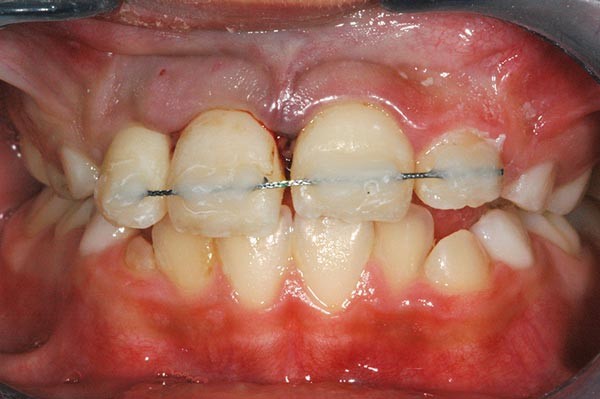

À l’examen clinique, le fragment coronaire peut être mobile, déplacé(fig. 1 et 2) et présenter une dyschromie transitoire de la couronne. Dès lors, un certain nombre de tests complémentaires s’impose.